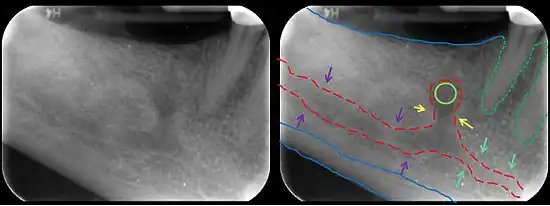

In human anatomy, the mandibular canal is a canal within the mandible that contains the inferior alveolar nerve, inferior alveolar artery, and inferior alveolar vein. It runs obliquely downward and forward in the ramus, and then horizontally forward in the body, where it is placed under the alveoli and communicates with them by small openings.

The mandibular canal is continuous with tow foramina: the mental foramen which opens in the mental region of the mandible and carried the distal fibres of the inferior alveolar nerve as the mental nerve; and the mandibular foramen on medial aspect of ramus, into which the mandibular nerve enters to become the inferior alveolar nerve. The mandibular canal often runs close to the apices of the third molar tooth, and the inferior alveolar nerve can become damaged during removal of this tooth, causing sensory disturbance in the distribution of the nerve. This is sometimes the case for the second or first molar teeth, and care must be taken during removal or root canal treatment in such cases to prevent nerve injury or extrusion of root canal filling materials.[2]

Variations

Several variations of the mandibular canal exist with varying frequency. The most common variant is the retromolar canal (~10 % of canals), whereby a branch is given off in the mandibular ramus which terminates in the retromolar region of the mandible. The retromolar canal may cause bleeding during surgery in the retromolar region such as removal of mandibular third molar teeth. Other variants include a bifid canal with a branch (~41%):[3] following the course of the main mandibular canal before re-joining it (forward or buccolingual type); terminating at the apex of a tooth, usually the molar teeth (dental type); opening as an accessory mental foramen.[4] A trifid mandibular canal variation has also been described.[5][6]